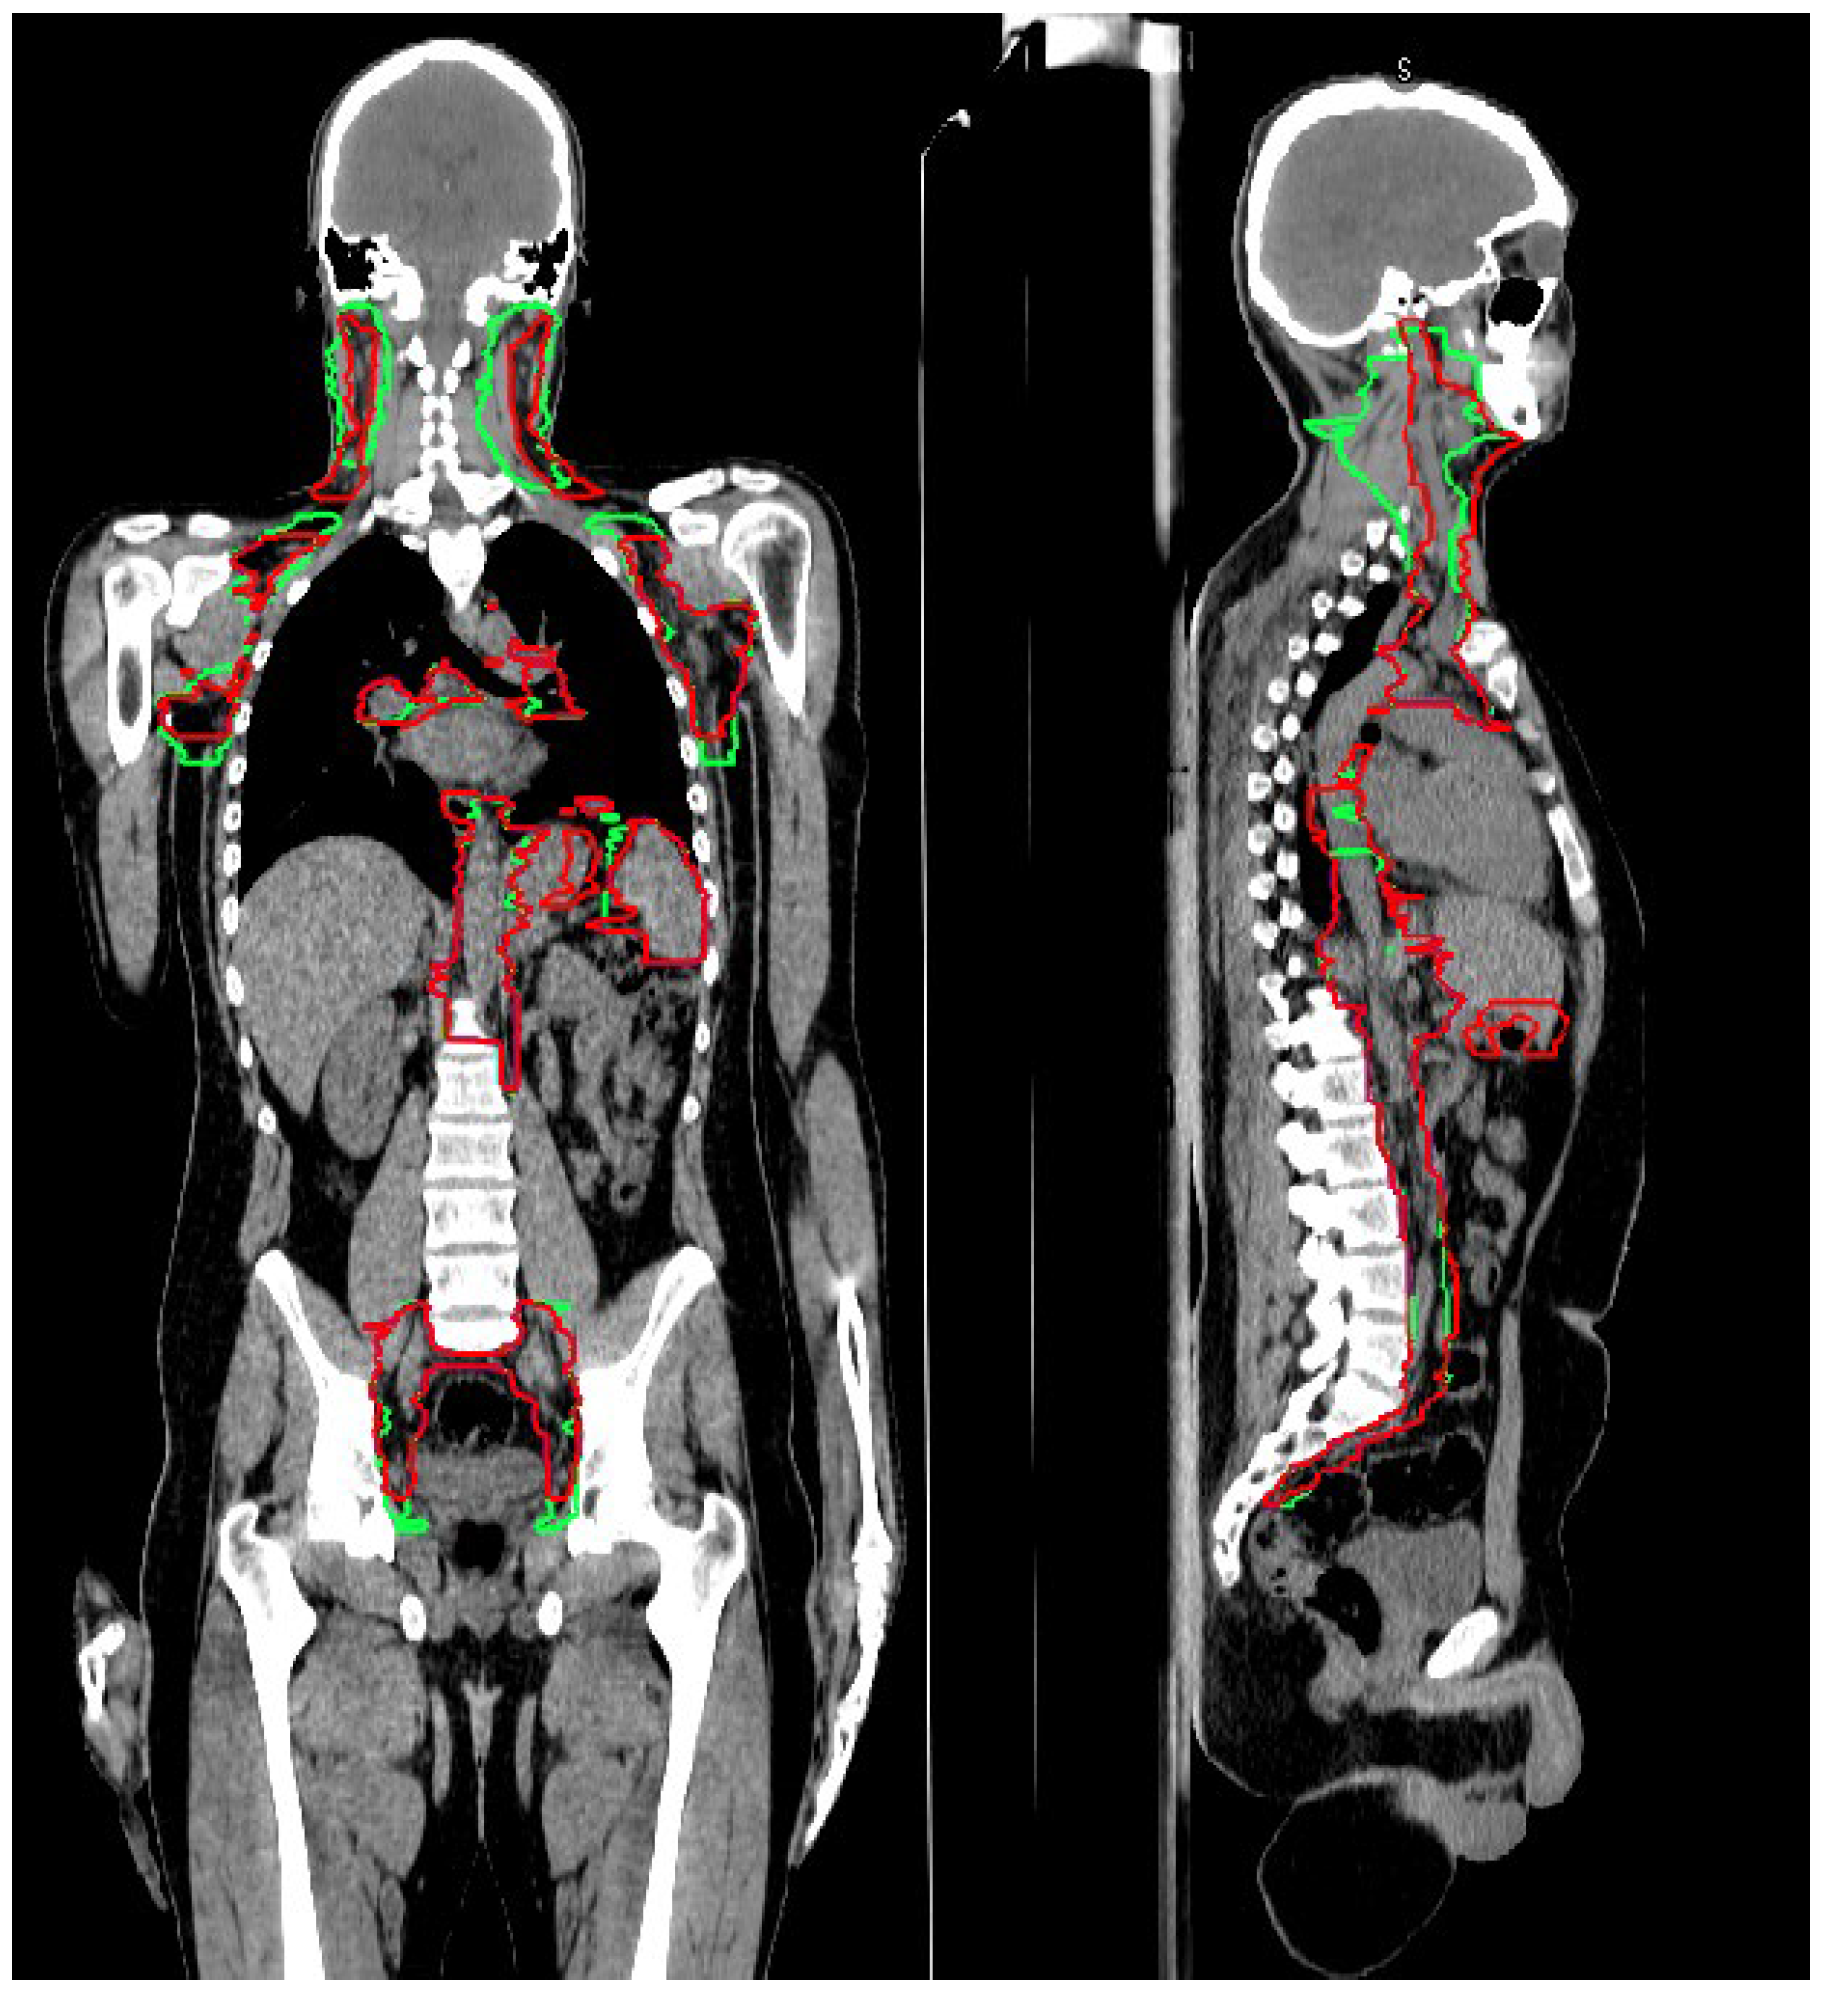

3.1. CTV_LN Inter-/Intraobserver Contouring Variability